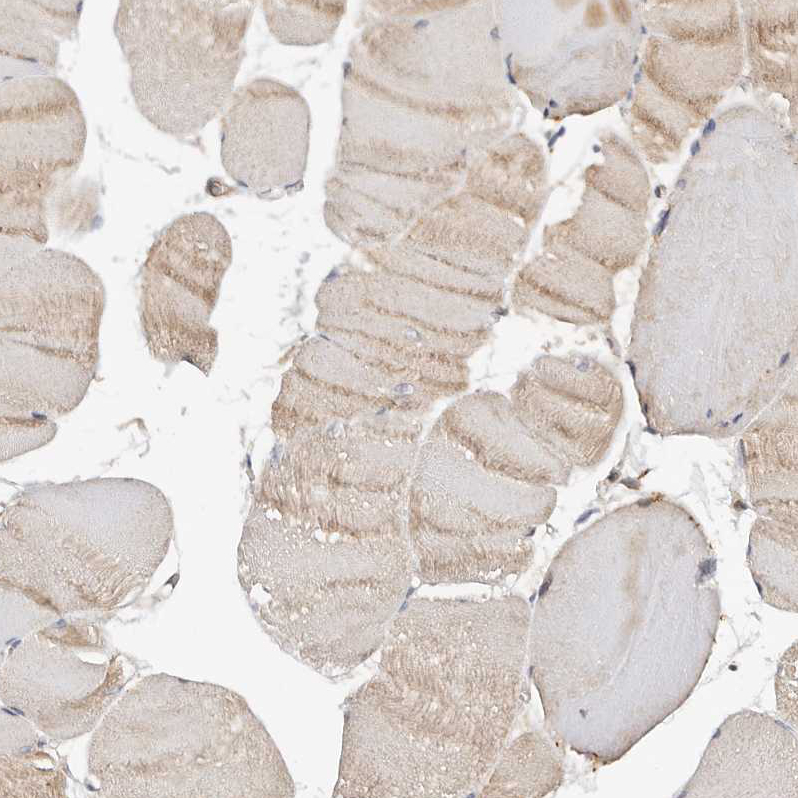

Immunohistochemical staining of human lung shows moderate cytoplasmic positivity in macrophages.